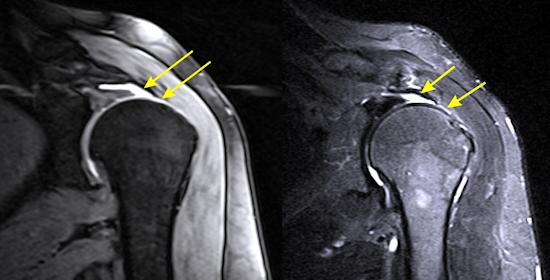

Omuz kas yırtıklarında artroskopik tedavi

Omuz çevresi kas yırtıkları sık görülen sorunlardır. Rotator manşet adı verilen bu kas grubu genç hastalarda şiddetli bir düşme veya travma sonrasına, yaşlı hastalarda ise aşınma/yıpranmaya bağlı olarak yırtılabilir. Omuz çevresi kas yırtıklarının en önemli bulgusu ağrıdır. Ağrı genellikle omuzun dış yanından başlayıp kolun ortasına kadar devam eder, genellikle kolunuzu yukarı kaldırırken ortaya çıkar.